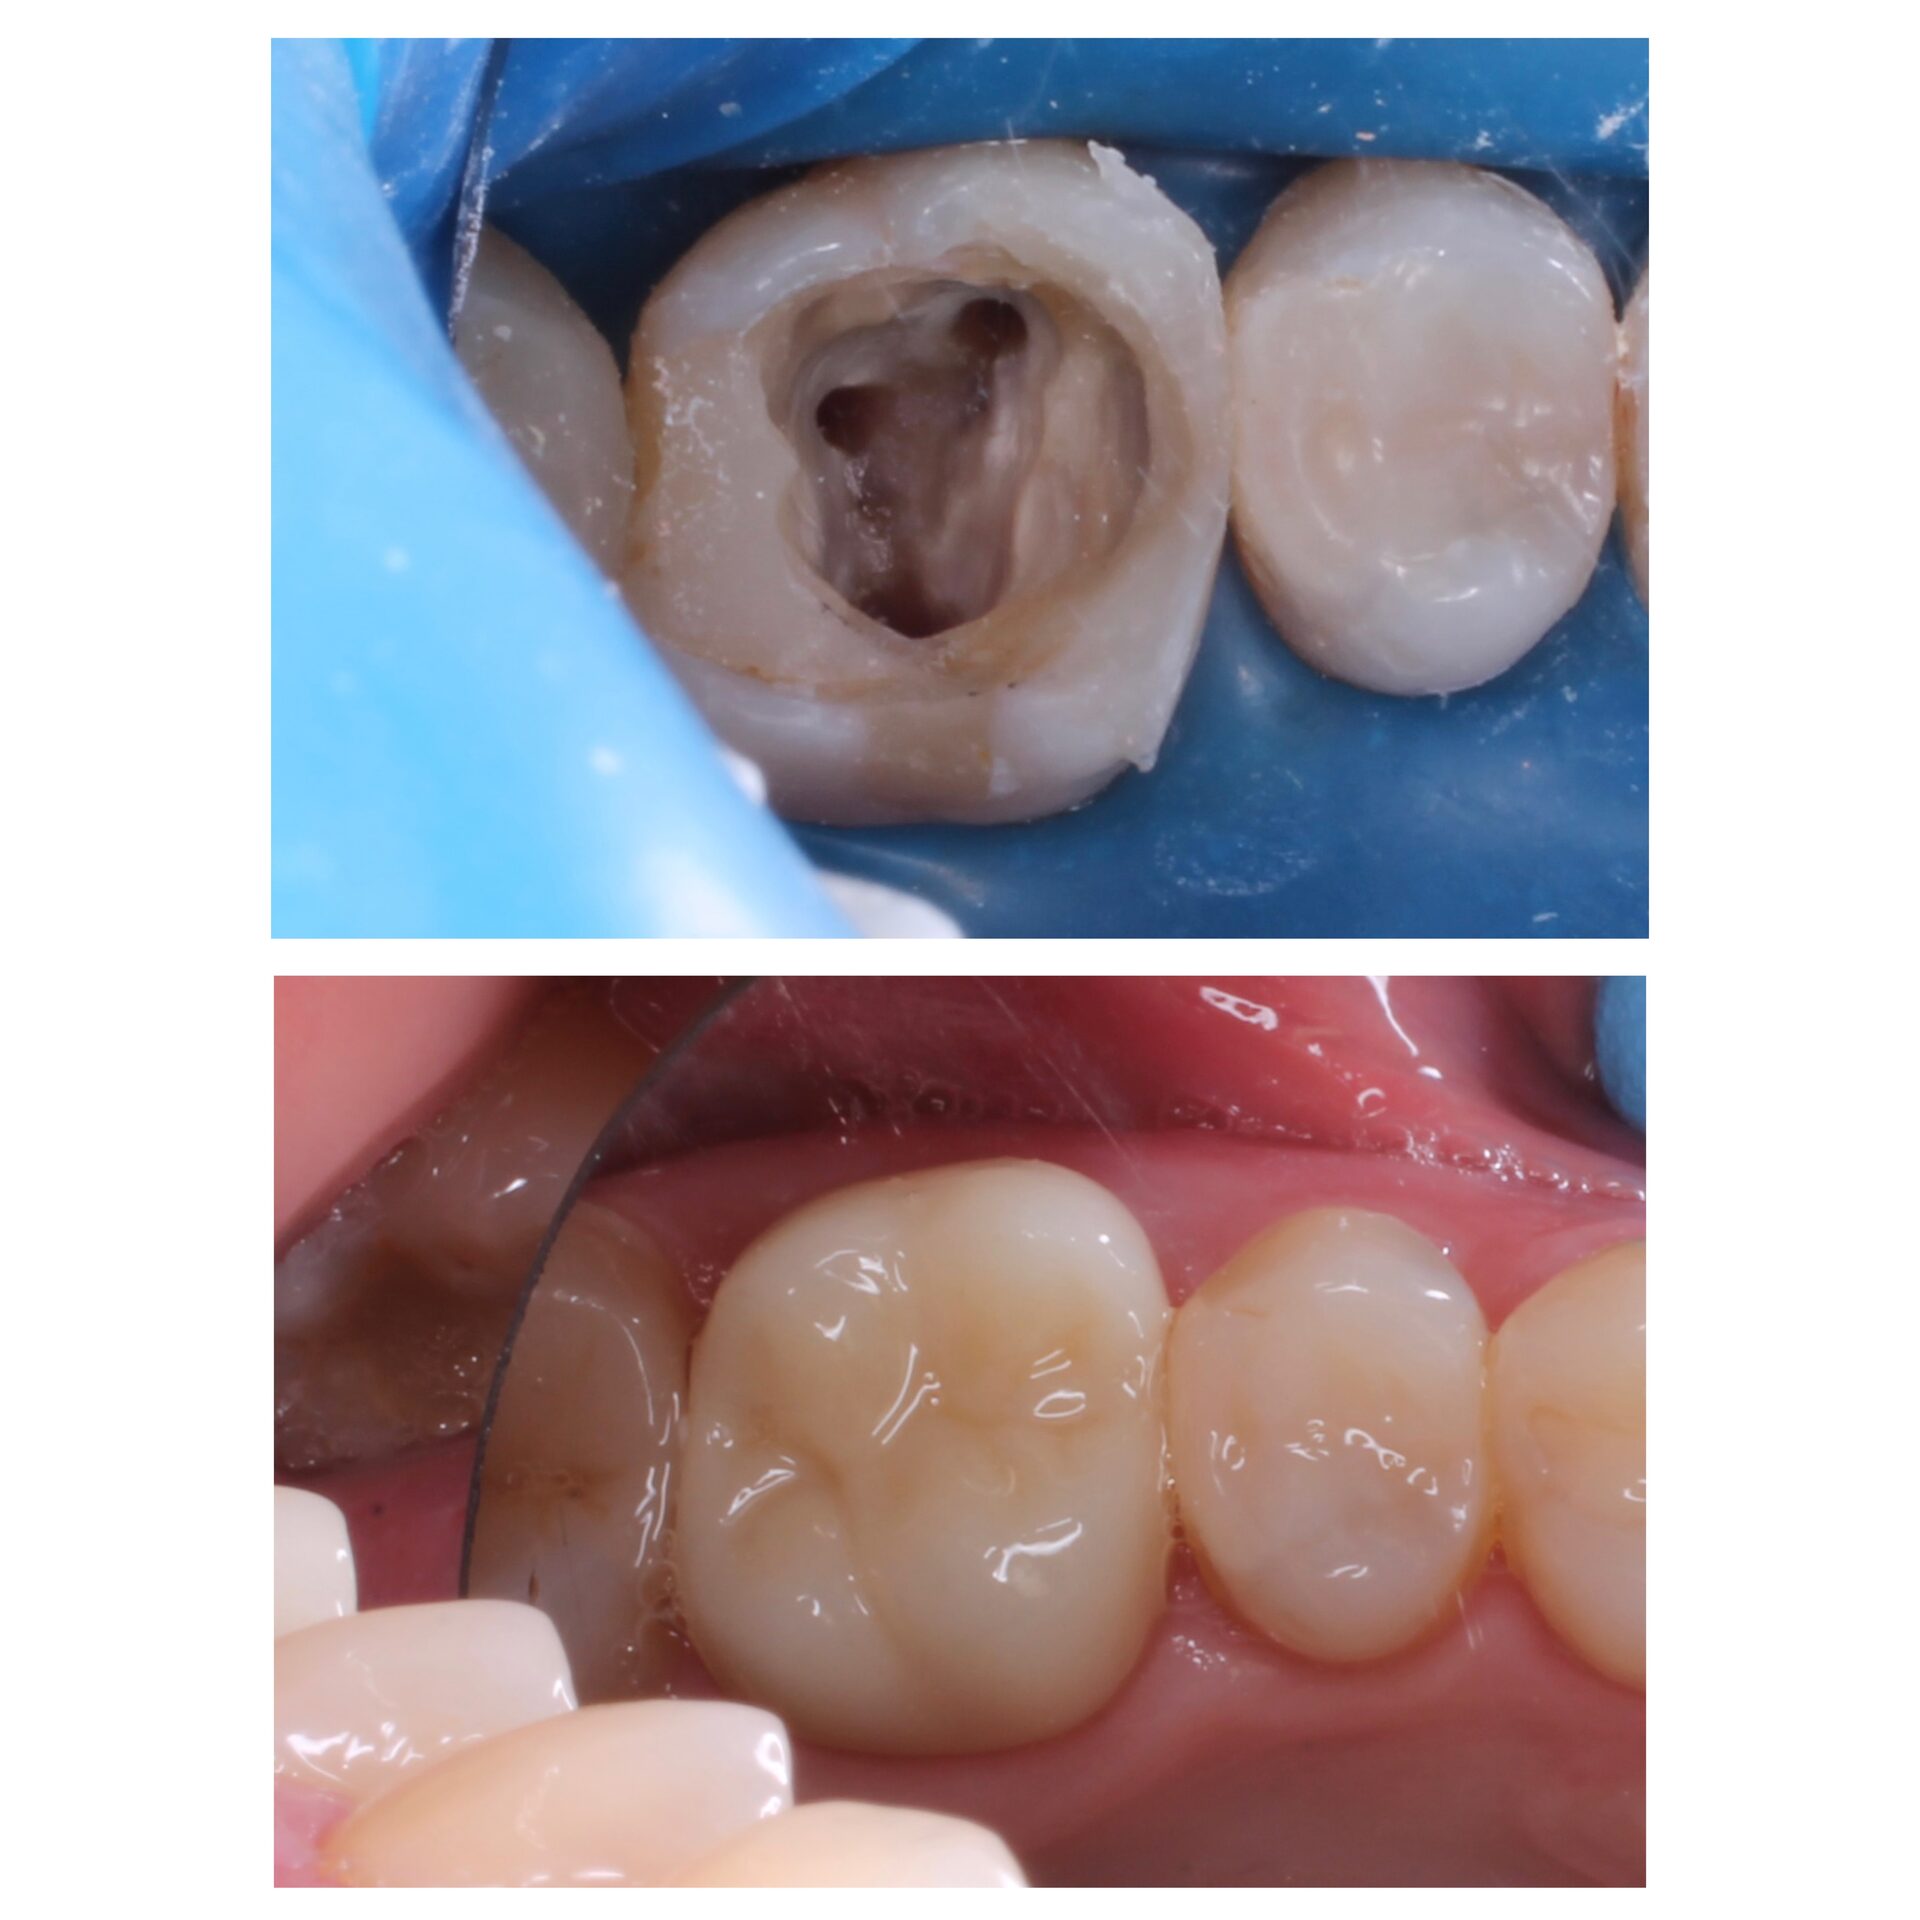

Лечение корневых каналов под микроскопом